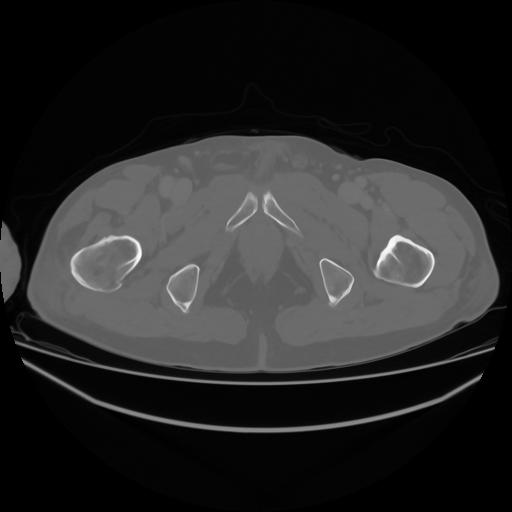

4 CUERPO,CE,Axial,3.0,CUERPO,,